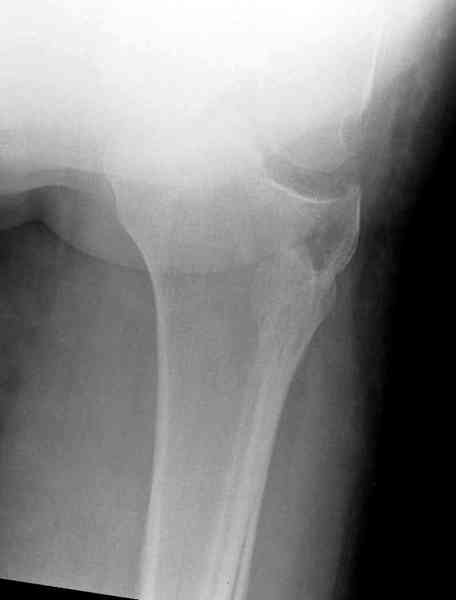

Здравствуйте, уважаемые коллеги!Подскажите, пожалуйста, какой выбрать доступ и способ фиксации при импрессионном переломе заднего отдела наружного мыщелка большеберцовой кости. Женщина 40 лет, травму получила 02.01.2008, катаясь на горных лыжах.Есть ли здесь необходимость использовать задний доступ, или можно справиться через наружный? Есть ли шансы сделать закрыто - под ЭОП через медиальное "окошко" поднять забойником суставную поврехность? Какой лучше использовать фиксатор?Спасибо.